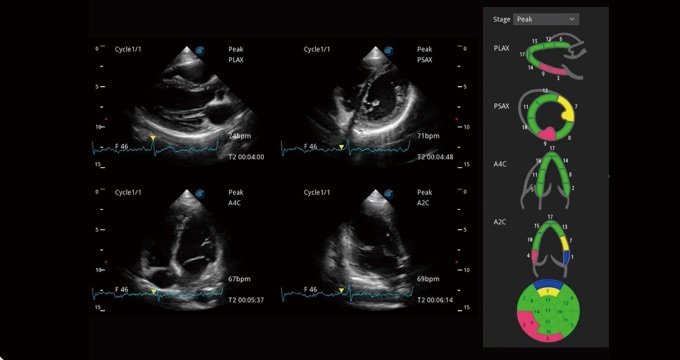

Stress-Echo

Eine unkomplizierte Vorlage für Kliniker, die mehrere dynamische Bilder in Ruhe und nach Belastung aufnehmen und nebeneinander vergleichen können. Für eine weitergehende effektive Abklärung der Vitalität des Herzmuskels werden professionelle Scores und Berichte zur Wandbewegung bereitgestellt.